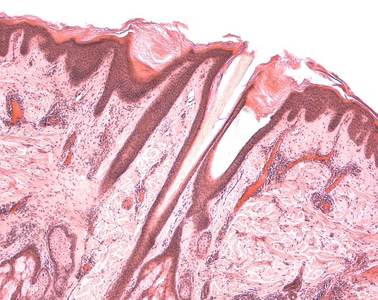

Präparat 97: Haare (Kopfhaut), Längsschnitt, H.-E.

gefäßlose, äußerste Schicht der Haut, besteht aus mehrschichtigem verhornten Plattenepithel, das einen fünfschichtigen Aufbau zeigt: Stratum basale, Stratum spinosum (Stratum basale und Stratum spinosum bilden gemeinsam das Stratum germinativum, die Regenerationsschicht der Haut), Stratum granulosum, Stratum lucidum (Str. granulosum und Str. lucidum bilden die Verhornungsschicht), Stratum corneum (Hornschicht).

Haartrichter

trichterförmige Erweiterung des Haarfollikels, hier münden die Talgdrüsen.

Bulbus pili

(Haarzwiebel) glockenförmige Auftreibung der Haarwurzel, die die bindegewebige Haarpapille umfaßt.

Auf der natürlichen Seite des Präparates erkennt man die Epidermis. Trichterförmige Einsenkungen der Epidermis reichen in die Tiefe, in jedem der Trichter findet sich ein Haar. Die Trichter enden in Form von sog. Haarzwiebeln (Bulbi pilorum) in der Subkutis. Unterhalb der Subkutis liegt die straff bindegewebige Galea aponeurotica (nicht in allen Präparaten zu sehen). Sie ist über kräftige Bindegewebsbrücken mit dem Stratum reticulare des Coriums verbunden; ihre Verbindung zu den darunterliegenden Knochen der Schädelkalotte ist schwach. Diese Konstruktion macht die Kopfhaut zu einem derben, beiderseits straff bindegewebigen Überzug des Schädels, dem Skalp, der sich leicht gegen den Schädel verschieben (und von ihm abziehen) läßt.